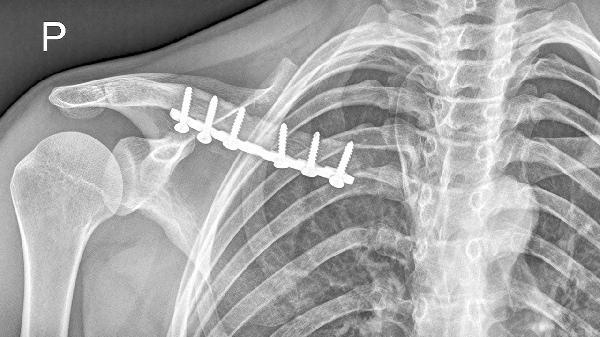

骨折線模糊是開始鍛煉的基礎(chǔ)指標(biāo),需通過X光確認(rèn)骨痂形成。臨床愈合通常需3-4周,此時(shí)可進(jìn)行被動(dòng)關(guān)節(jié)活動(dòng)。完全負(fù)重訓(xùn)練需等待骨性愈合,約需8-12周。

第一階段0-2周進(jìn)行手指腕部活動(dòng),第二階段2-4周增加肘關(guān)節(jié)屈伸,第三階段4周后逐步開展肩關(guān)節(jié)鐘擺運(yùn)動(dòng)。物理治療師會(huì)根據(jù)肌力測(cè)試制定個(gè)性化方案。